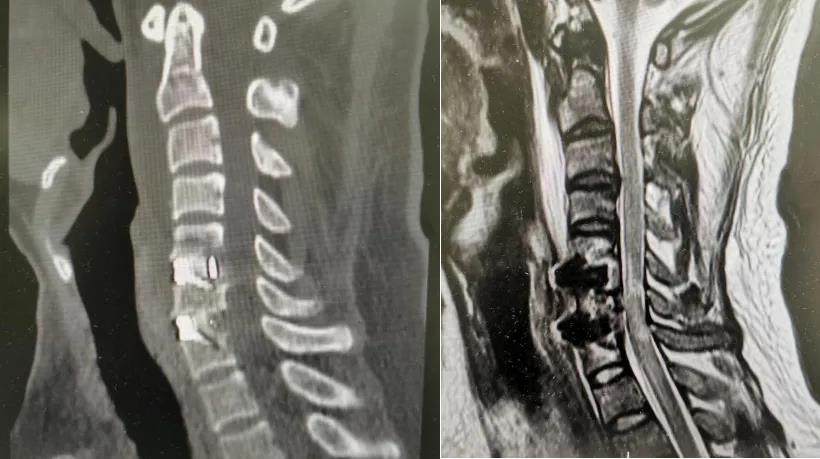

2025年12月22日,由脊柱微创科主任王义生教授作为指导,在麻醉科和手术室的密切配合下,唐福兴博士借助内镜系统的高清视野,为患者精准、彻底地清除致压物,解除颈脊髓和神经根压迫,并于椎间隙植入零切迹融合器重建颈椎稳定性。这整个过程,好比工程师们利用先进设备,将隧道中阻塞的“淤泥”和“塌方”彻底清除,并重新加固其结构,使其宽敞而稳固,不再受阻。术后第一天,患者即感觉肢体疼痛、麻木明显缓解,肢体力量改善,可佩戴颈托下地活动。术后复查CT和MRI显示致压物得到彻底切除,脊髓减压充分、内固定位置良好。

▲C5/6、C6/7节段致压物完全切除,脊髓减压充分、内固定位置良好(左:术后颈椎CT;右:术后颈椎MRI)